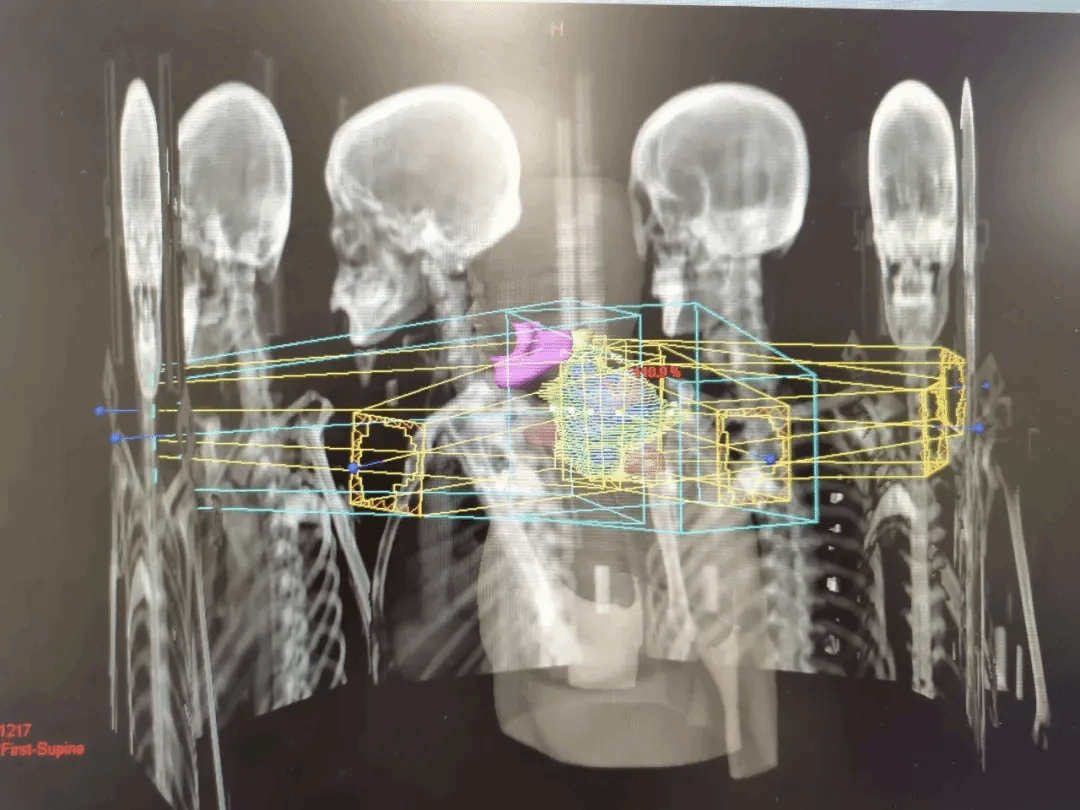

3.靶区勾画与计划设计:核心的“作战计划”——放疗医生在CT影像上,逐层勾勒:

·肿瘤靶区:需要直接打击的“主战场”。

·临床靶区:包含可能潜藏的微小病灶。

·计划靶区:考虑到呼吸、器官移动和日常摆位误差,设立的“安全边界”。

物理师随后利用配套的计算机计划系统,进行复杂的剂量计算,最大限度将能量聚焦于肿瘤,同时让周围正常组织(如脊髓、心脏、肠管)的受照剂量降至最低。这个过程可能需要数天,需要耐心等待,这是精准和安全的前提。